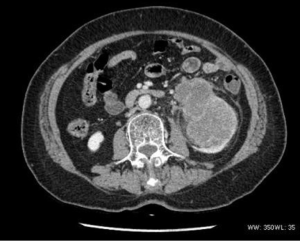

The renal tumor case revealed a moderate heterogeneous enhancement, blurred boundary with the renal pelvis, and thickening of the perirenal fascia (Figure 4).